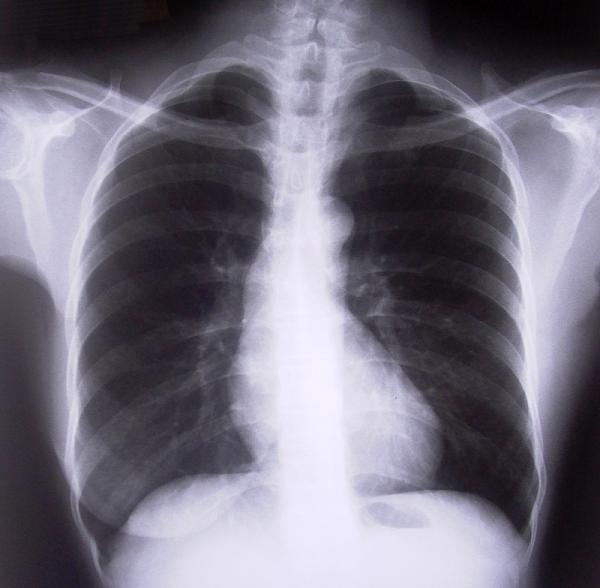

Si has sufrido un golpe fuerte, una caída o un accidente y sospechas que tienes una o varias costillas rotas, deberás acudir de inmediato a un hospital para realizar los exámenes oportunos y confirmar el diagnóstico, pues será necesaria la opinión médica para confirmar si la fractura pone en peligro los pulmones o cualquier otro órgano.

Dependiendo de la gravedad de la fractura será necesario mantenerte en observación médica para asegurar que tus pulmones y corazón no corren peligro. Las complicaciones en este tipo de casos residen fundamentalmente en la dificultad para respirar que pueden sufrir algunos pacientes, si no es tu caso entonces podrás ser dado de alta y continuar con los cuidados desde casa.